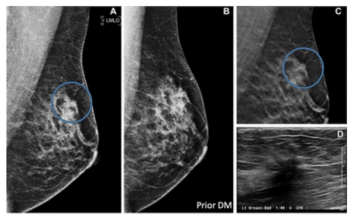

A symptomatic first breast cancer diagnosis, prevailing breast density at a second breast cancer diagnosis and trabecular thickening on surveillance mammography were linked to mammogram-occult ipsilateral breast cancer, according to new research.

While researchers noted no significant impact on sensitivity rates, they found that access to a patient’s prior mammograms resulted in a nearly 15 percent increase in sensitivity for current mammography interpretation.